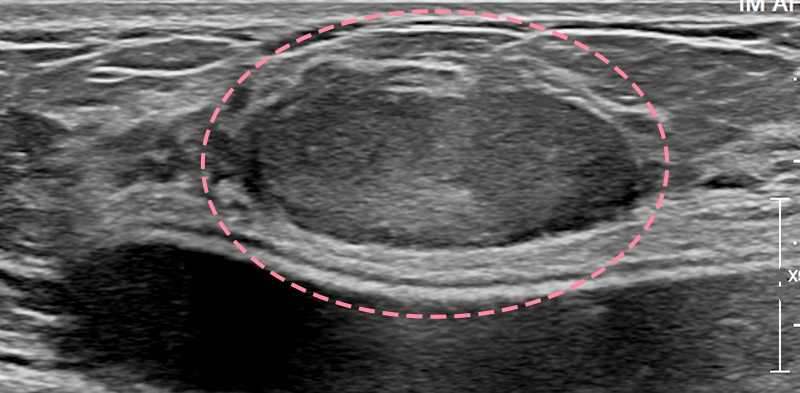

매우 빠르게 자라는 유방 종양 수술을 위해 외국에서 내원한 17세 환자의 사례입니다.

3cm 이상의 유방 종양은 외과적 수술로 제거하는 것이 원칙이고, 대부분의 경우 대학병원으로 연계됩니다.

그러나 한송이 원장은 대학병원에서의 고난도 시술 경력을 다수 보유하고 있어 크기가 큰 종양도 맘모톰 시술로 가능하였습니다.

3번에 걸쳐 맘모톰시술을 시행한 결과 성공적으로 제거를 마칠 수 있었습니다. 외과적 절제로 생길 수 있었을 흉터를 원치 않으셨던 환자와 보호자분 모두 시술 결과에 만족하셨습니다. 매년 추적 검사를 시행하고 있으며, 깨끗이 제거된 상태를 잘 유지하는 중입니다.